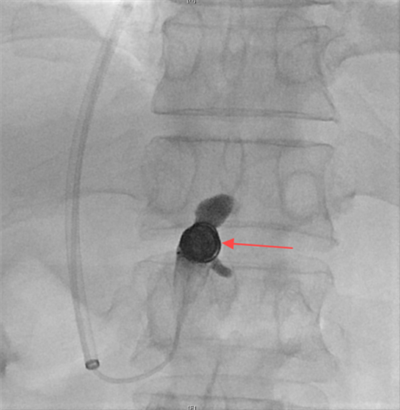

随后,赵扬程介入手术团队决定为患者施行经颈静脉肝内门体分流术(TIPS),术中经颈静脉入路精准植入8毫米覆膜支架,于肝静脉与门静脉间构建分流通道,同步完成食管胃底曲张静脉栓塞。术后门静脉压力由36厘米水柱降至20厘米水柱,出血立即停止,血红蛋白水平稳定回升。该手术在有效降低血管压力的同时维持肝脏血流灌注,为患者争取到后续治疗的宝贵时间窗。

图一:肝穿刺针成功进入肝门静脉

图二:胃底静脉成功栓塞

图三:肝门静脉及支架内血流通畅